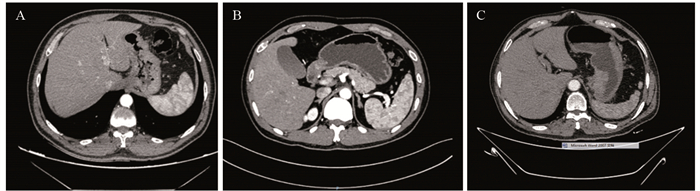

方法回顾性分析268例胃癌患者的临床病理资料。患者术前常规行薄层增强CT评估术前N分期,结合术后病理结果分析术前N分期不足的危险因素。Logistic回归分析筛选出的影响因素,Kaplan-Meier绘制术前N分期准确组与不足组的生存曲线,利用R软件包绘制Nomogram图、预测模型的ROC曲线,计算AUC、95%CI、敏感度和特异性。

MethodsA retrospective method was used to analyze the clinicopathological data of 268 patients with gastric cancer. The patients routinely underwent preoperative thin-section enhanced CT to assess preoperative N-stage. Results The risk factors for preoperative N-stage deficiency were analyzed in combination with postoperative pathological findings. Multifactorial logistic regression analysis was performed to determine influencing factors, and Kaplan-Meier analysis was used to plot the survival curves of preoperative N-stage accurate group and deficiency group. The nomogram plot and ROC curves of the prediction model were drawn using the R package. AUC, 95%CI, sensitivity, and specificity were calculated.